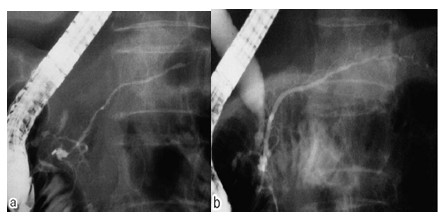

a:胰管狭窄

b:治疗后狭窄的胰管恢复正常